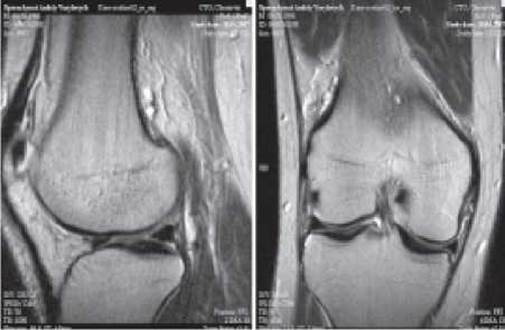

На зображеннях, отриманих за допомогою магнітно-резонансної томографії, добре відрізняються одне від одного м’язи, сухожилки, зв’язки, хрящі, жир, рідина, тому цей вид томографії більш чутливий при дослідженні змін, що виникають у м’яких тканинах і кістковому мозку, проте не дає змоги дослідити тонку структуру кістки і виявити звапнення. МРТ і КТ дозволяють також проводити дослідження при гіпсовій іммобілізації кінцівки (мал. 29).

Мал. 29. Магнітно-резонансна томограма коліна (Т2-зважене зображення) у сагітальній та фронтальній площинах.